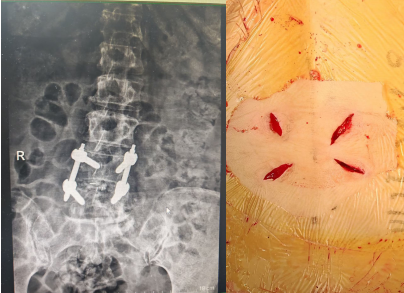

该患者半年前出现腰部及右下肢的疼痛,但休息后尚能缓解最近症状加重,身体出现侧弯,严重影响了日常生活。患者四处求医,但一直因惧怕开放手术的创伤,故一直未选择手术治疗。了解到苏州高新区人民医院一直开展的微创脊柱内镜手术,遂前来就诊,行核磁共振检查后,发现腰4椎体向前明显滑脱,椎间盘突出,椎管狭窄,压迫左侧神经根需要行腰椎滑脱椎间盘切除,椎管减压,滑脱复位,椎间植骨融合内固定手术。医院骨科脊柱微创中心刘勇主任团队为她制定了微创手术方案,腰部创面非常小。

术后患者恢复顺利,术后六天即顺利下地行走,步态正常,原腰疼和下肢疼痛,麻木症状消失,患者对手术效果非常满意。医院脊柱微创中心自2020年成立以来,依托多项微创技术,对脊柱患者尤其腰椎间盘突出症的患者进行微创手术治疗,从单纯的椎间盘突出,椎管狭窄到严重的腰椎滑脱,均可采用微创手术解除患者病痛,为此也树立了良好的口碑。